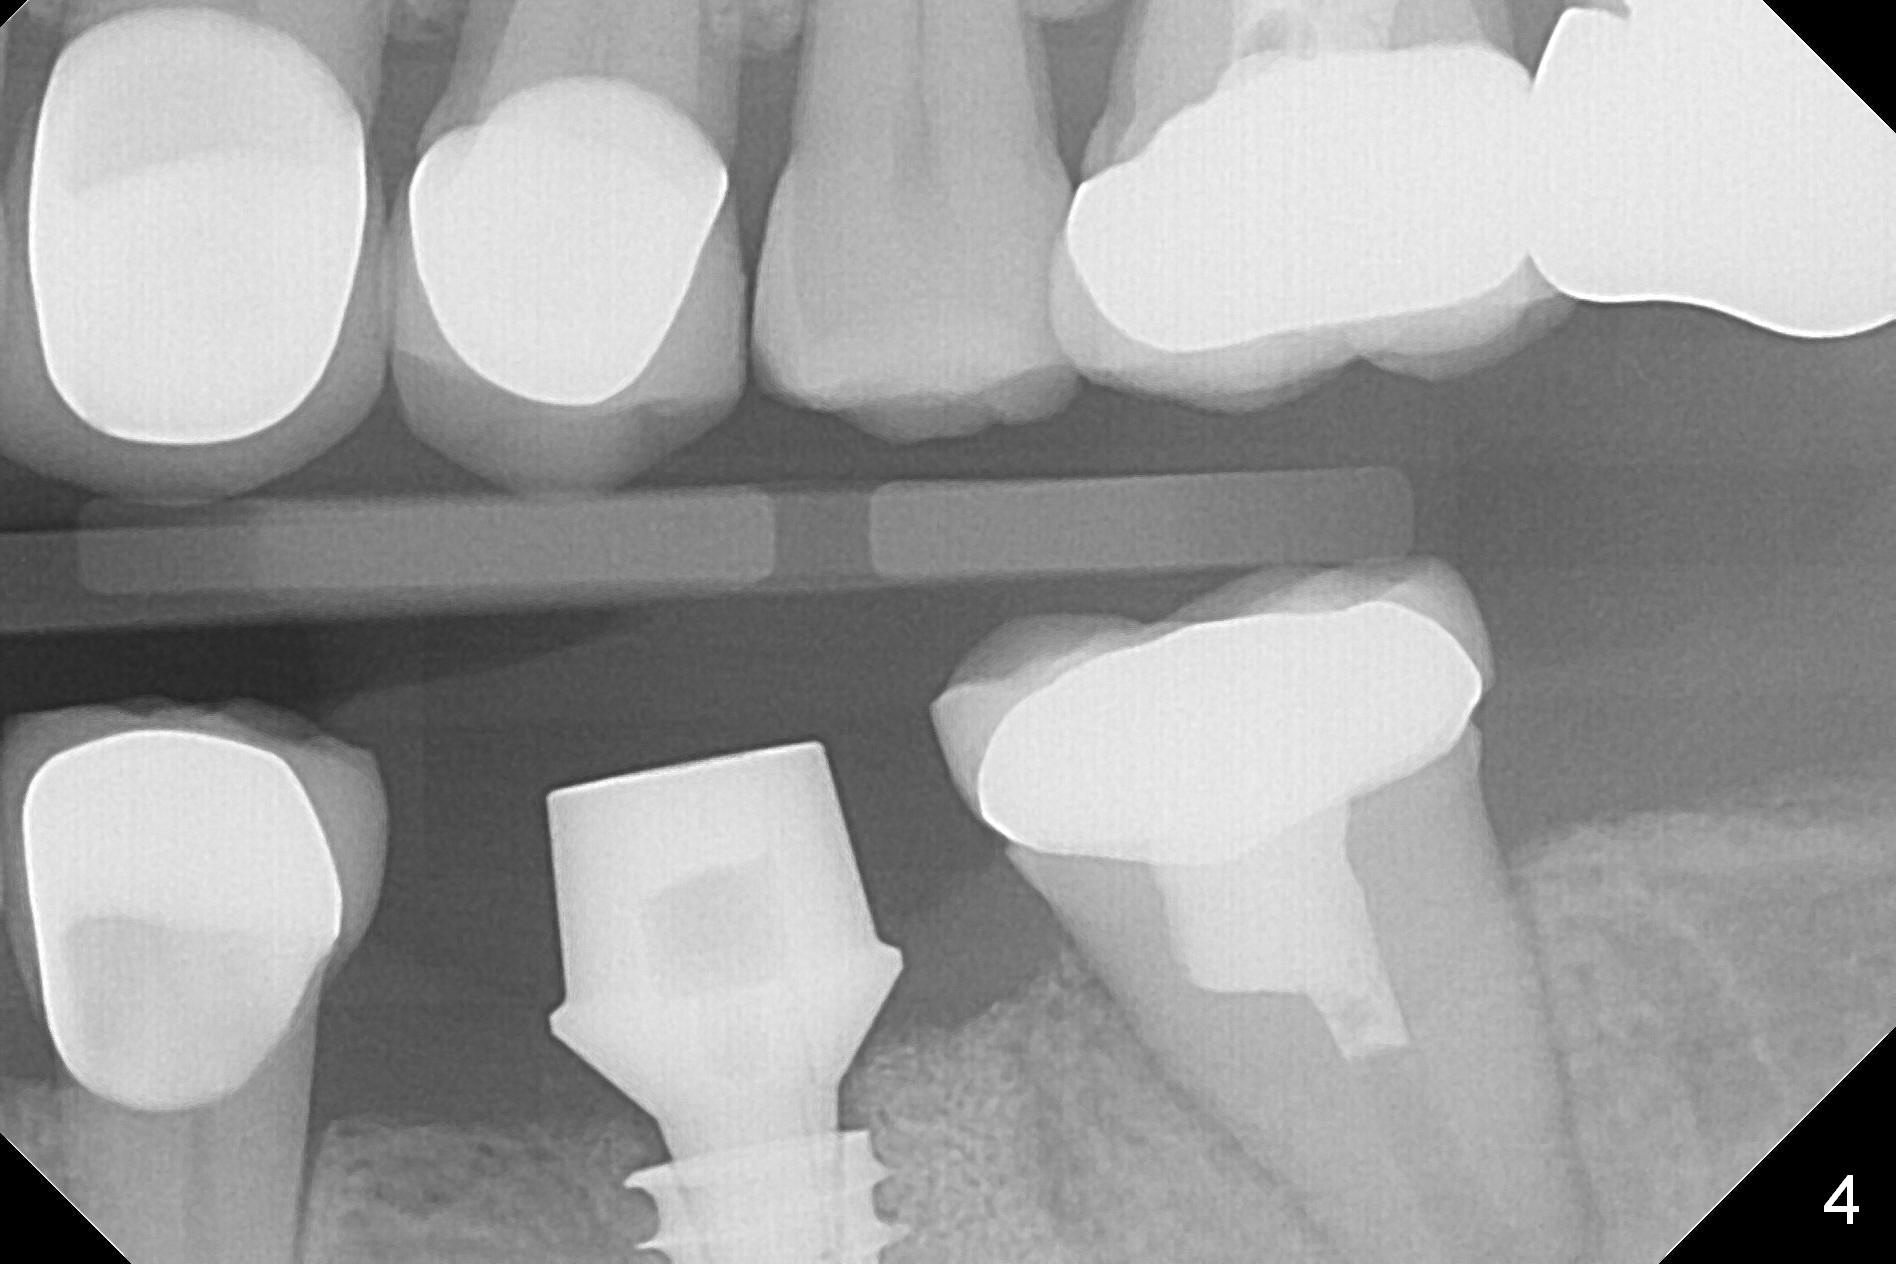

After making a 10 mm incision at the site of #19, #15c blade is used as an osteotome to start bone expansion, followed by Magic Split and Magic Expander (ME, 3 mm in diameter). The depth is approximately the bottom of the mesial socket. The osteotomy beyond the socket has to be done with 1.6 mm pilot drill (Fig.1) in combination of ME. Following ME 4.3 mm and Magic Drill (MD) 3.8 mm for 15 mm (gingival level), a 4.5x11 mm dummy implant is placed with 50 Ncm (Fig.3); the implant looks narrow for the edentulous space. After ME 4.8, MD 4.3 for 13 mm and Final Drill for 15 mm, a 5x11 mm IBS is inserted with >50 Ncm (Fig.3). With 2 more turns of the implant, a 6.5x4(2) mm abutment is placed (Fig.4). Periodontal dressing is applied around the abutment for additional retention. A provisional is fabricated 3 weeks postop. The provisional and abutment are loose 4 months postop (Fig.5). After retightening the abutment, impression is taken for final restoration. There is no bone loss 1 year 3 months post cementation (Fig.6). After use of #100 file (Fig.7), the canal is debrided with #140 file with 1.5 mm shorter in working length with placement of Calcium Hydroxide paste. Pain gets worse post RCT retreatment. There is limited native bone for primary stability when an immediate implant is placed (red dashed line: the superior border of the Inferior Alveolar Canal). Prepare IS regular and extra wide kits and tissue-level implants (>5 mm). Socket preservation may be done instead. If the socket is large and the vein is not so small, prepare PRF. In fact blood drawing fails. When the tooth is extracted, it is sensitive to remove granulation tissue. Socket preservation is done with Vanilla graft at #18 (Fig.8); there is ~3.5 mm bone between the bottom of the single socket and the Inferior Alveolar Canal (red dashed line). The socket at #18 seems to have healed 4 months post extraction (Fig.19), but the bone height appears to have been reduced (compare Fig.10,11). The buccolingual width is also decreased (Fig.12,13). A 4.5 or 5.0x10 mm implant is appropriate for the site (Fig.14). There is no bone loss at #19 (which may be associated with the bone expansion) 1.5 years post cementation (Fig.15). Therefore the osteotomy at #18 will be assisted with bone expanders after 2.2 mm drill.